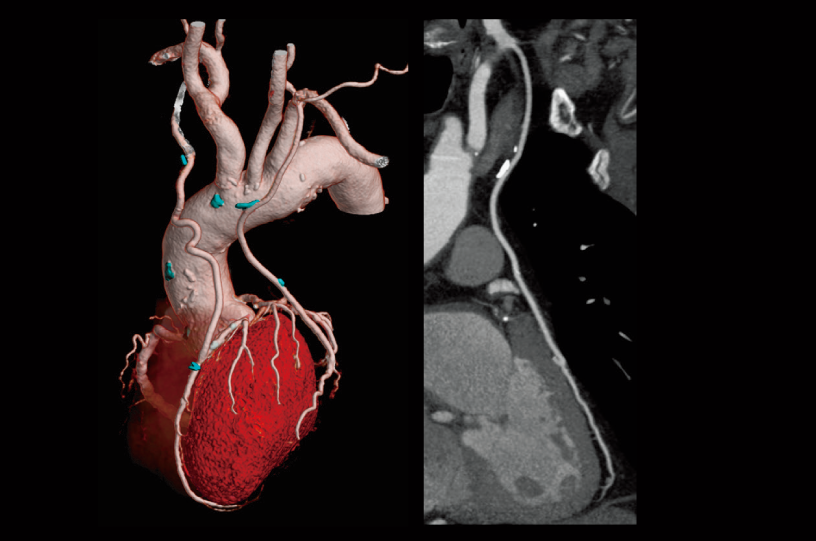

Follow-up after CABG

Aortic valve (Cardio StillShot)